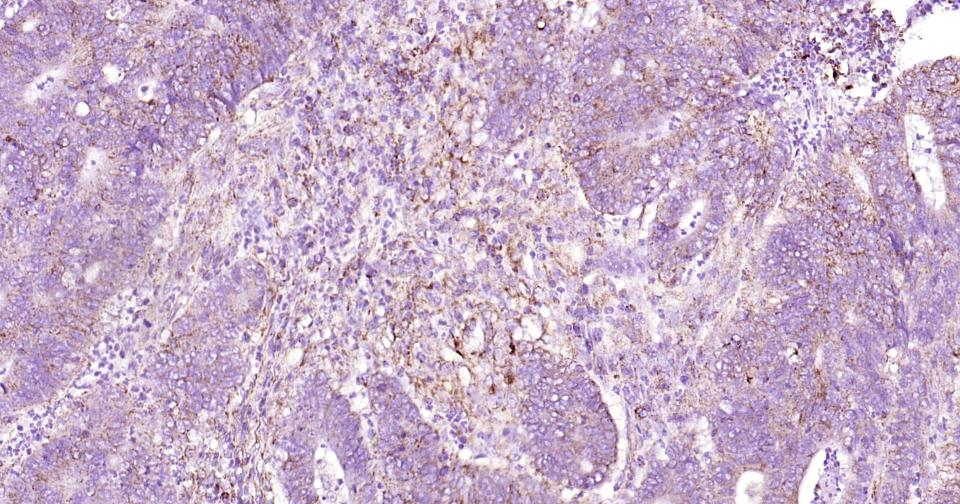

Paraformaldehyde-fixed, paraffin embedded Human Pancreatic Cancer; Antigen retrieval by boiling in sodium citrate buffer (pH6.0) for 15 min; Antibody incubation with Osteopontin? Monoclonal Antibody, Unconjugated(bsm-43600R) at 1:200 overnight at 4°C, followed by conjugation to the SP Kit (Rabbit, SP-0023)and DAB (C-0010) staining.